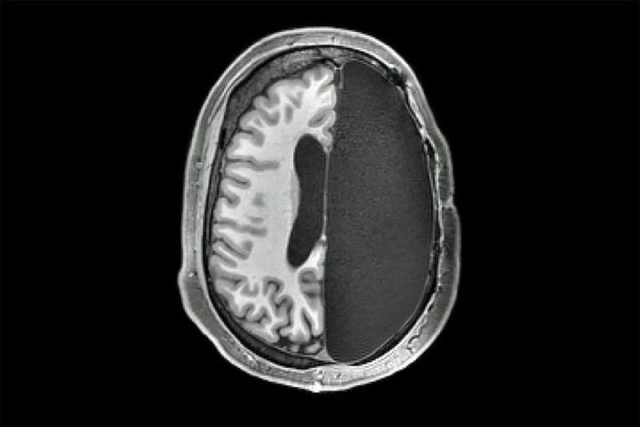

一般来说 , 颅脑损伤 , 有颅内出血、脑损伤的情况下 , 需要进行了去骨瓣减压手术 。 也就是掀开头皮 , 露出颅骨 , 然后用电钻和锯子去掉一块颅骨 , 暴露出受损的脑部 , 才能进行治疗 , 或止血 , 或切除坏死组织 , 或清除血液、血块 。 完成这些后 , 依次缝合硬脑膜和头皮 , 而之前去掉的颅骨就不会再“装”回去了 。

一般术后10天 , 水肿完全消退 , 去掉骨瓣的地方就会瘪下去;由于李女士伤情比较严重 , 去除的骨瓣比较多 , 可能达半边颅骨 , 所以术后头部看起来有缺损 , 局部塌陷 , 就像没了半个脑袋一样 。